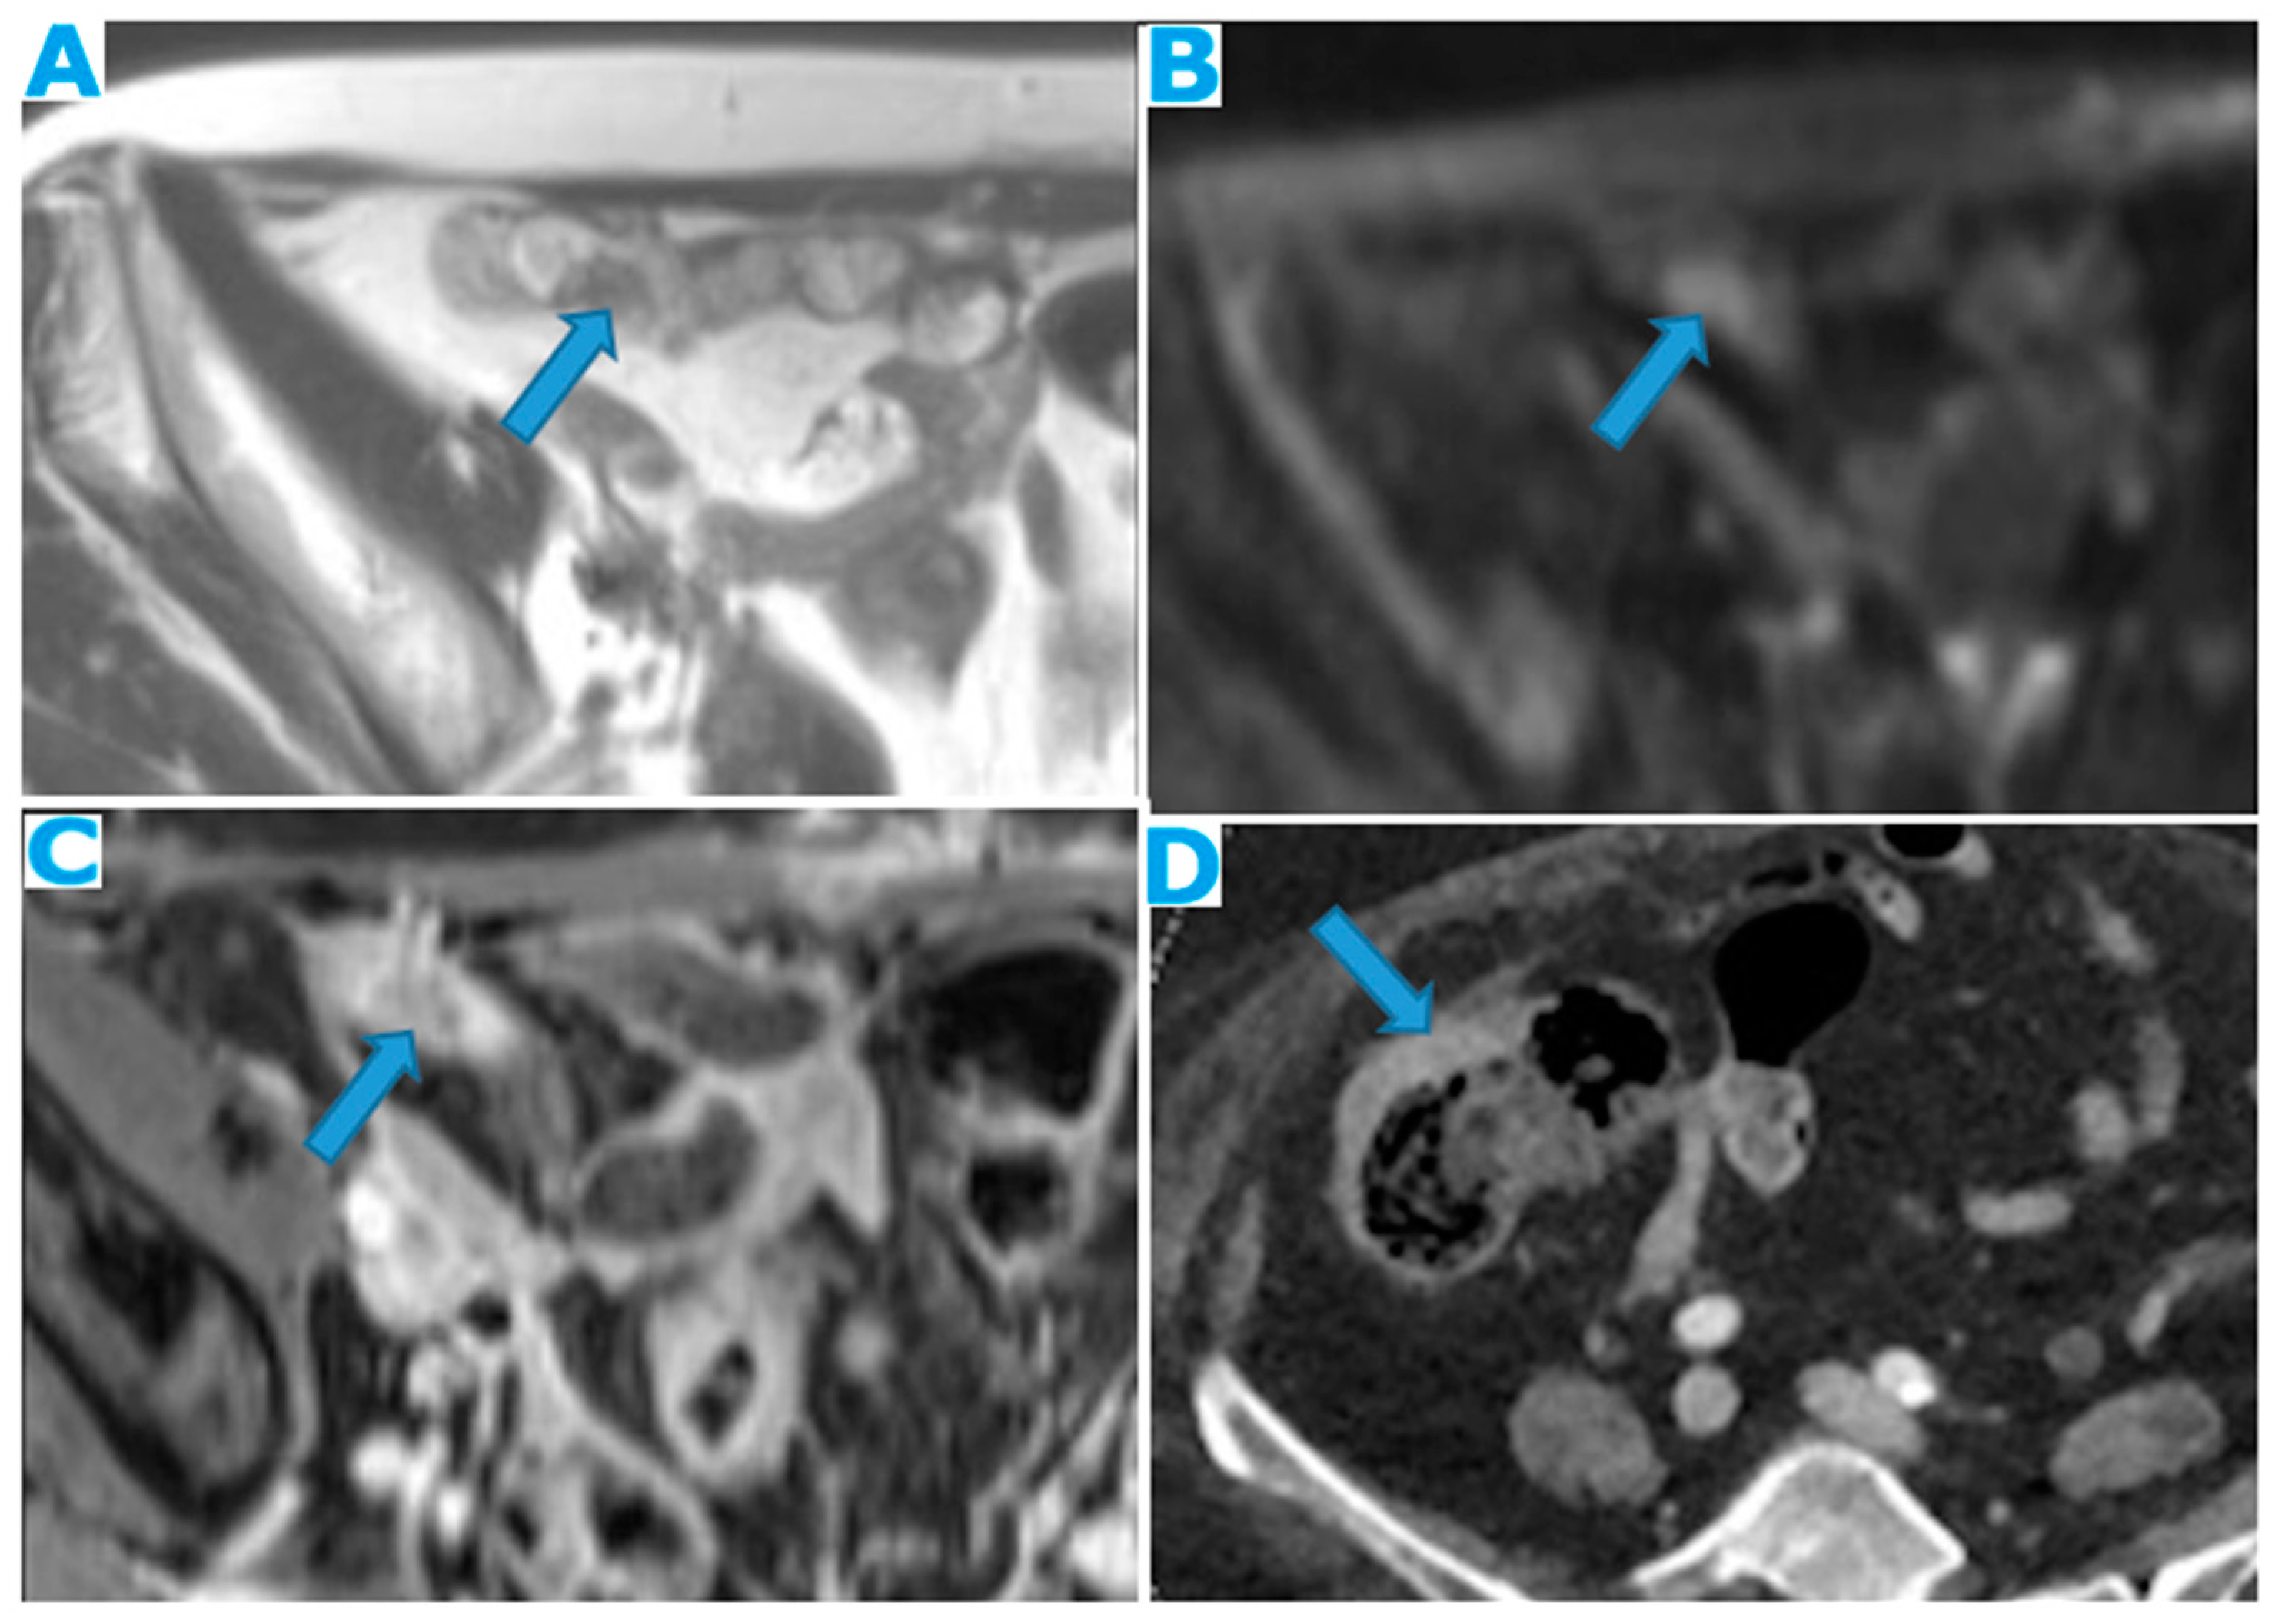

Figure 22.

Axial T2WI (A), axial DWI (B), CE portal phase FST1WI (C). PC from duodenal adenocarcinoma: Deposit within the distal ileum serosa. Axial CE-CT (D). PC from breast carcinoma: Deposits within the caecal serosa.